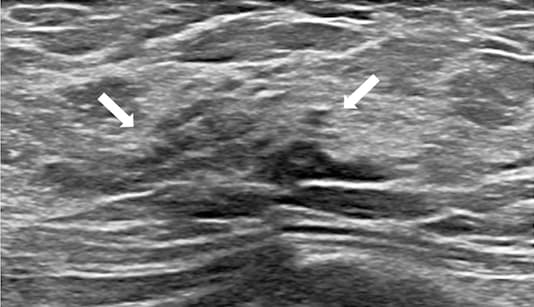

Les lésions nodulaires malignes mammaires sont jugées comme difficilement standardisées dans BI-RADS. Une étude coréenne publiée dans la Revue Radiology tente de faire une comparaison avec les lésions non tumorales et observe une bonne concordance inter-observateurs pour le classement en lésions neuromusculaires, tandis que des classifications différentes sont proposées selon les comparaisons avec la mammographie ou l’IRM.